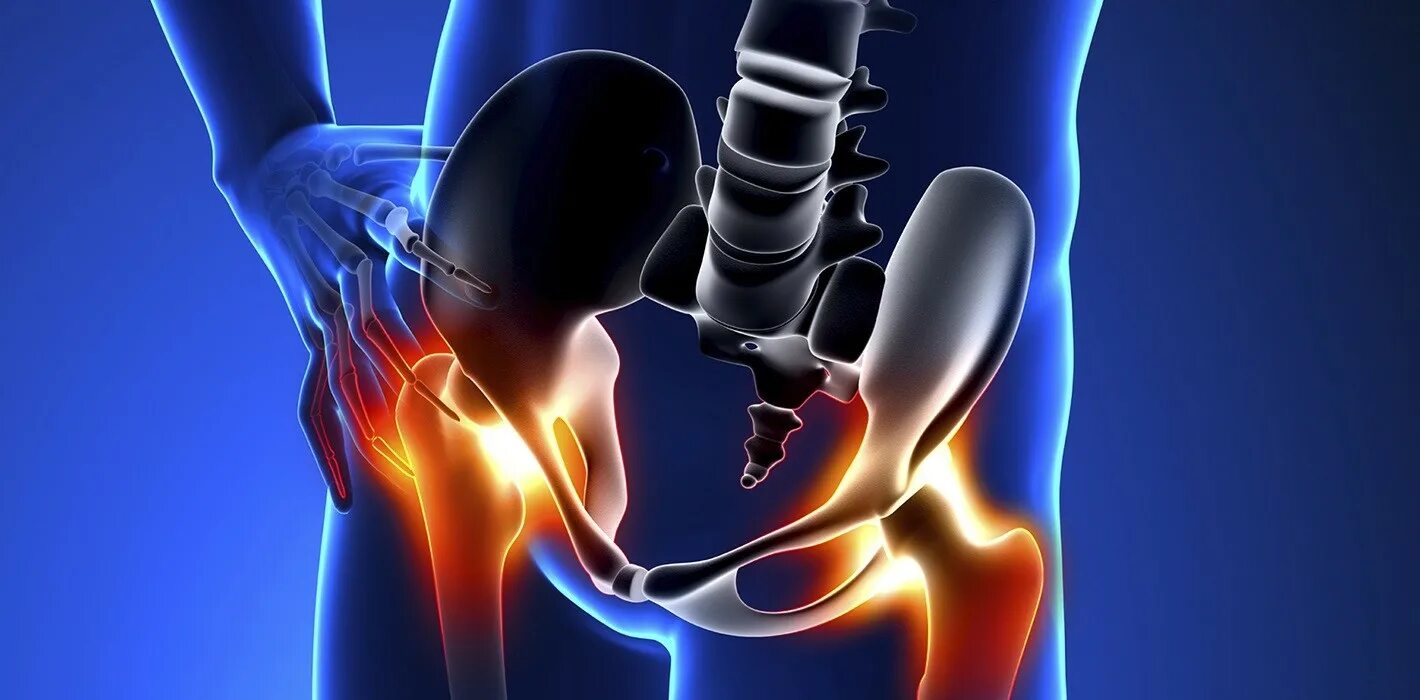

Как лечить синовит тазобедренного сустава